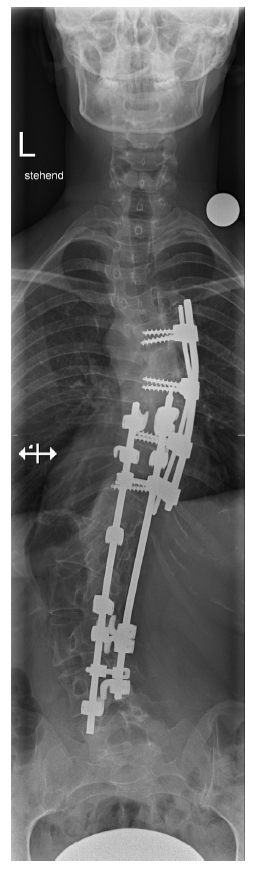

病例阐述

图1:脊柱侧凸手术后的正位X线片。